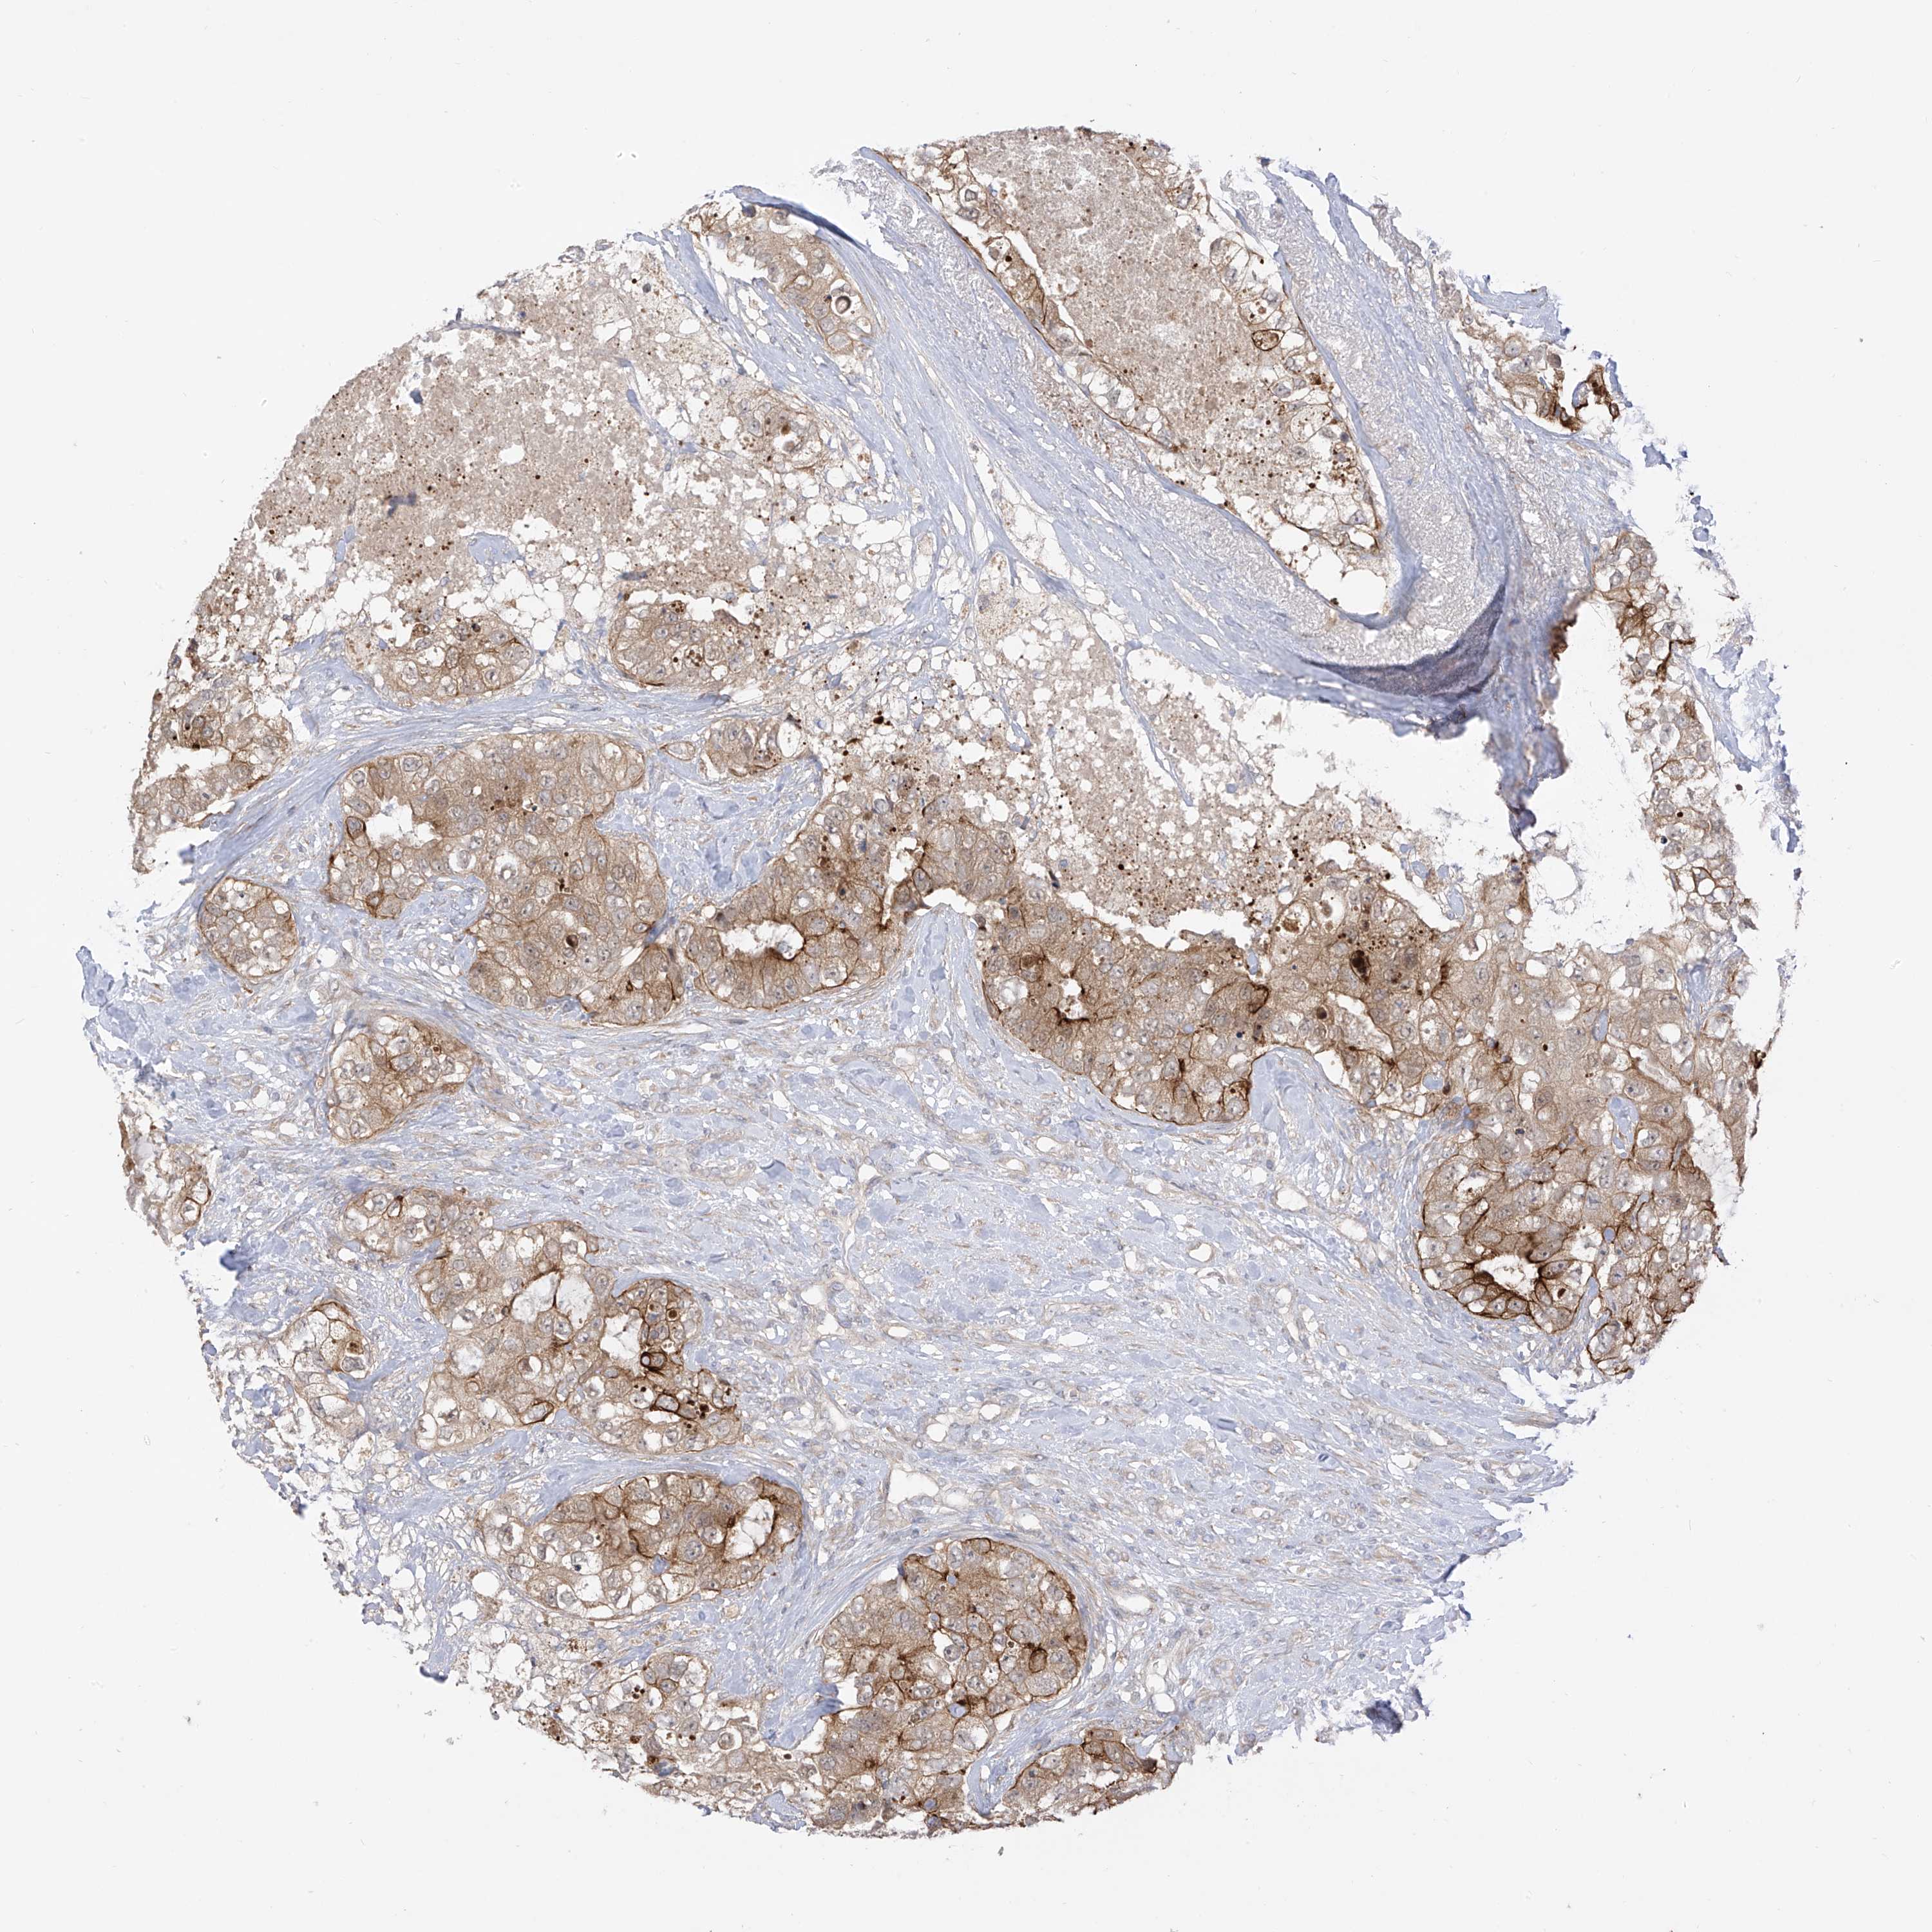

CANCER BREAST CANCER Show tissue menu

BRCA TCGA BRCA VALIDATION PROTEIN EXPRESSION